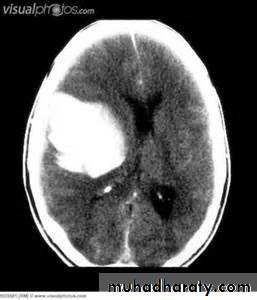

the principle imaging for ICH is CT scanning

Intracranial hemorrhage

hemorrhage, or bleeding, within the cranial vault [skull] Either within the meninges or parenchymal bleedingtypes

IntracerebralCAPSULER